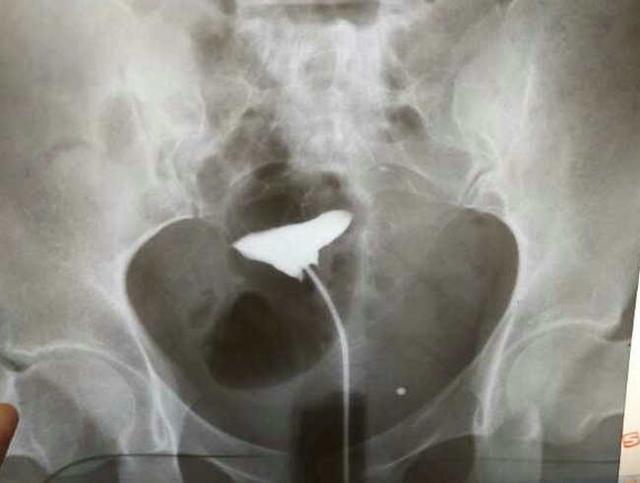

健康的育龄女性,每个月经周期内都会排出一枚发育成熟的卵子,在卵细胞发育的过程中,不但卵泡的体积会不断增大、卵泡液变多,卵泡还会逐渐向卵巢表面转移,突出于卵巢的包膜上。等到卵细胞完全发育成熟,卵巢包膜就会溶解、破裂,卵泡液排出,卵子被缓慢地挤出卵巢,这就是排卵。